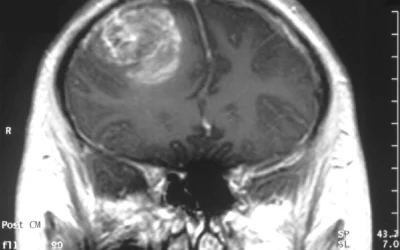

Mokslininkai atrado naują glioblastomos augimą skatinančių smegenų ląstelių tinklą

Kanados mokslininkai atrado netikėtą glioblastomos, vienos iš pavojingiausių smegenų vėžio formų, silpnybę. Tyrimo metu nustatyta, kad tam tikros smegenų ląstelės, anksčiau laikytos tik normalios nervų…